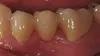

Crowns (Caps)

Before: Patient needs a Single Tooth Replacement of one Upper Central Incisor. After: Smile and function restored with a Single Implant and an All Porcelain Crown (Cap) that fits securely over the implant.